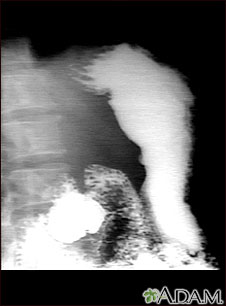

Radiografía de úlcera estomacal

Este es un ejemplo de un procedimiento llamado serie GI superior. La persona ingiere una sustancia llamada bario, que permite que se iluminen los órganos bajo estudio en la radiografía. En este caso, el paciente presenta una ulceración en el estómago que se puede observar en la parte derecha de la pantalla. Este método se utiliza para diagnosticar úlceras estomacales así como otras anomalías a lo largo del tracto gastrointestinal superior.